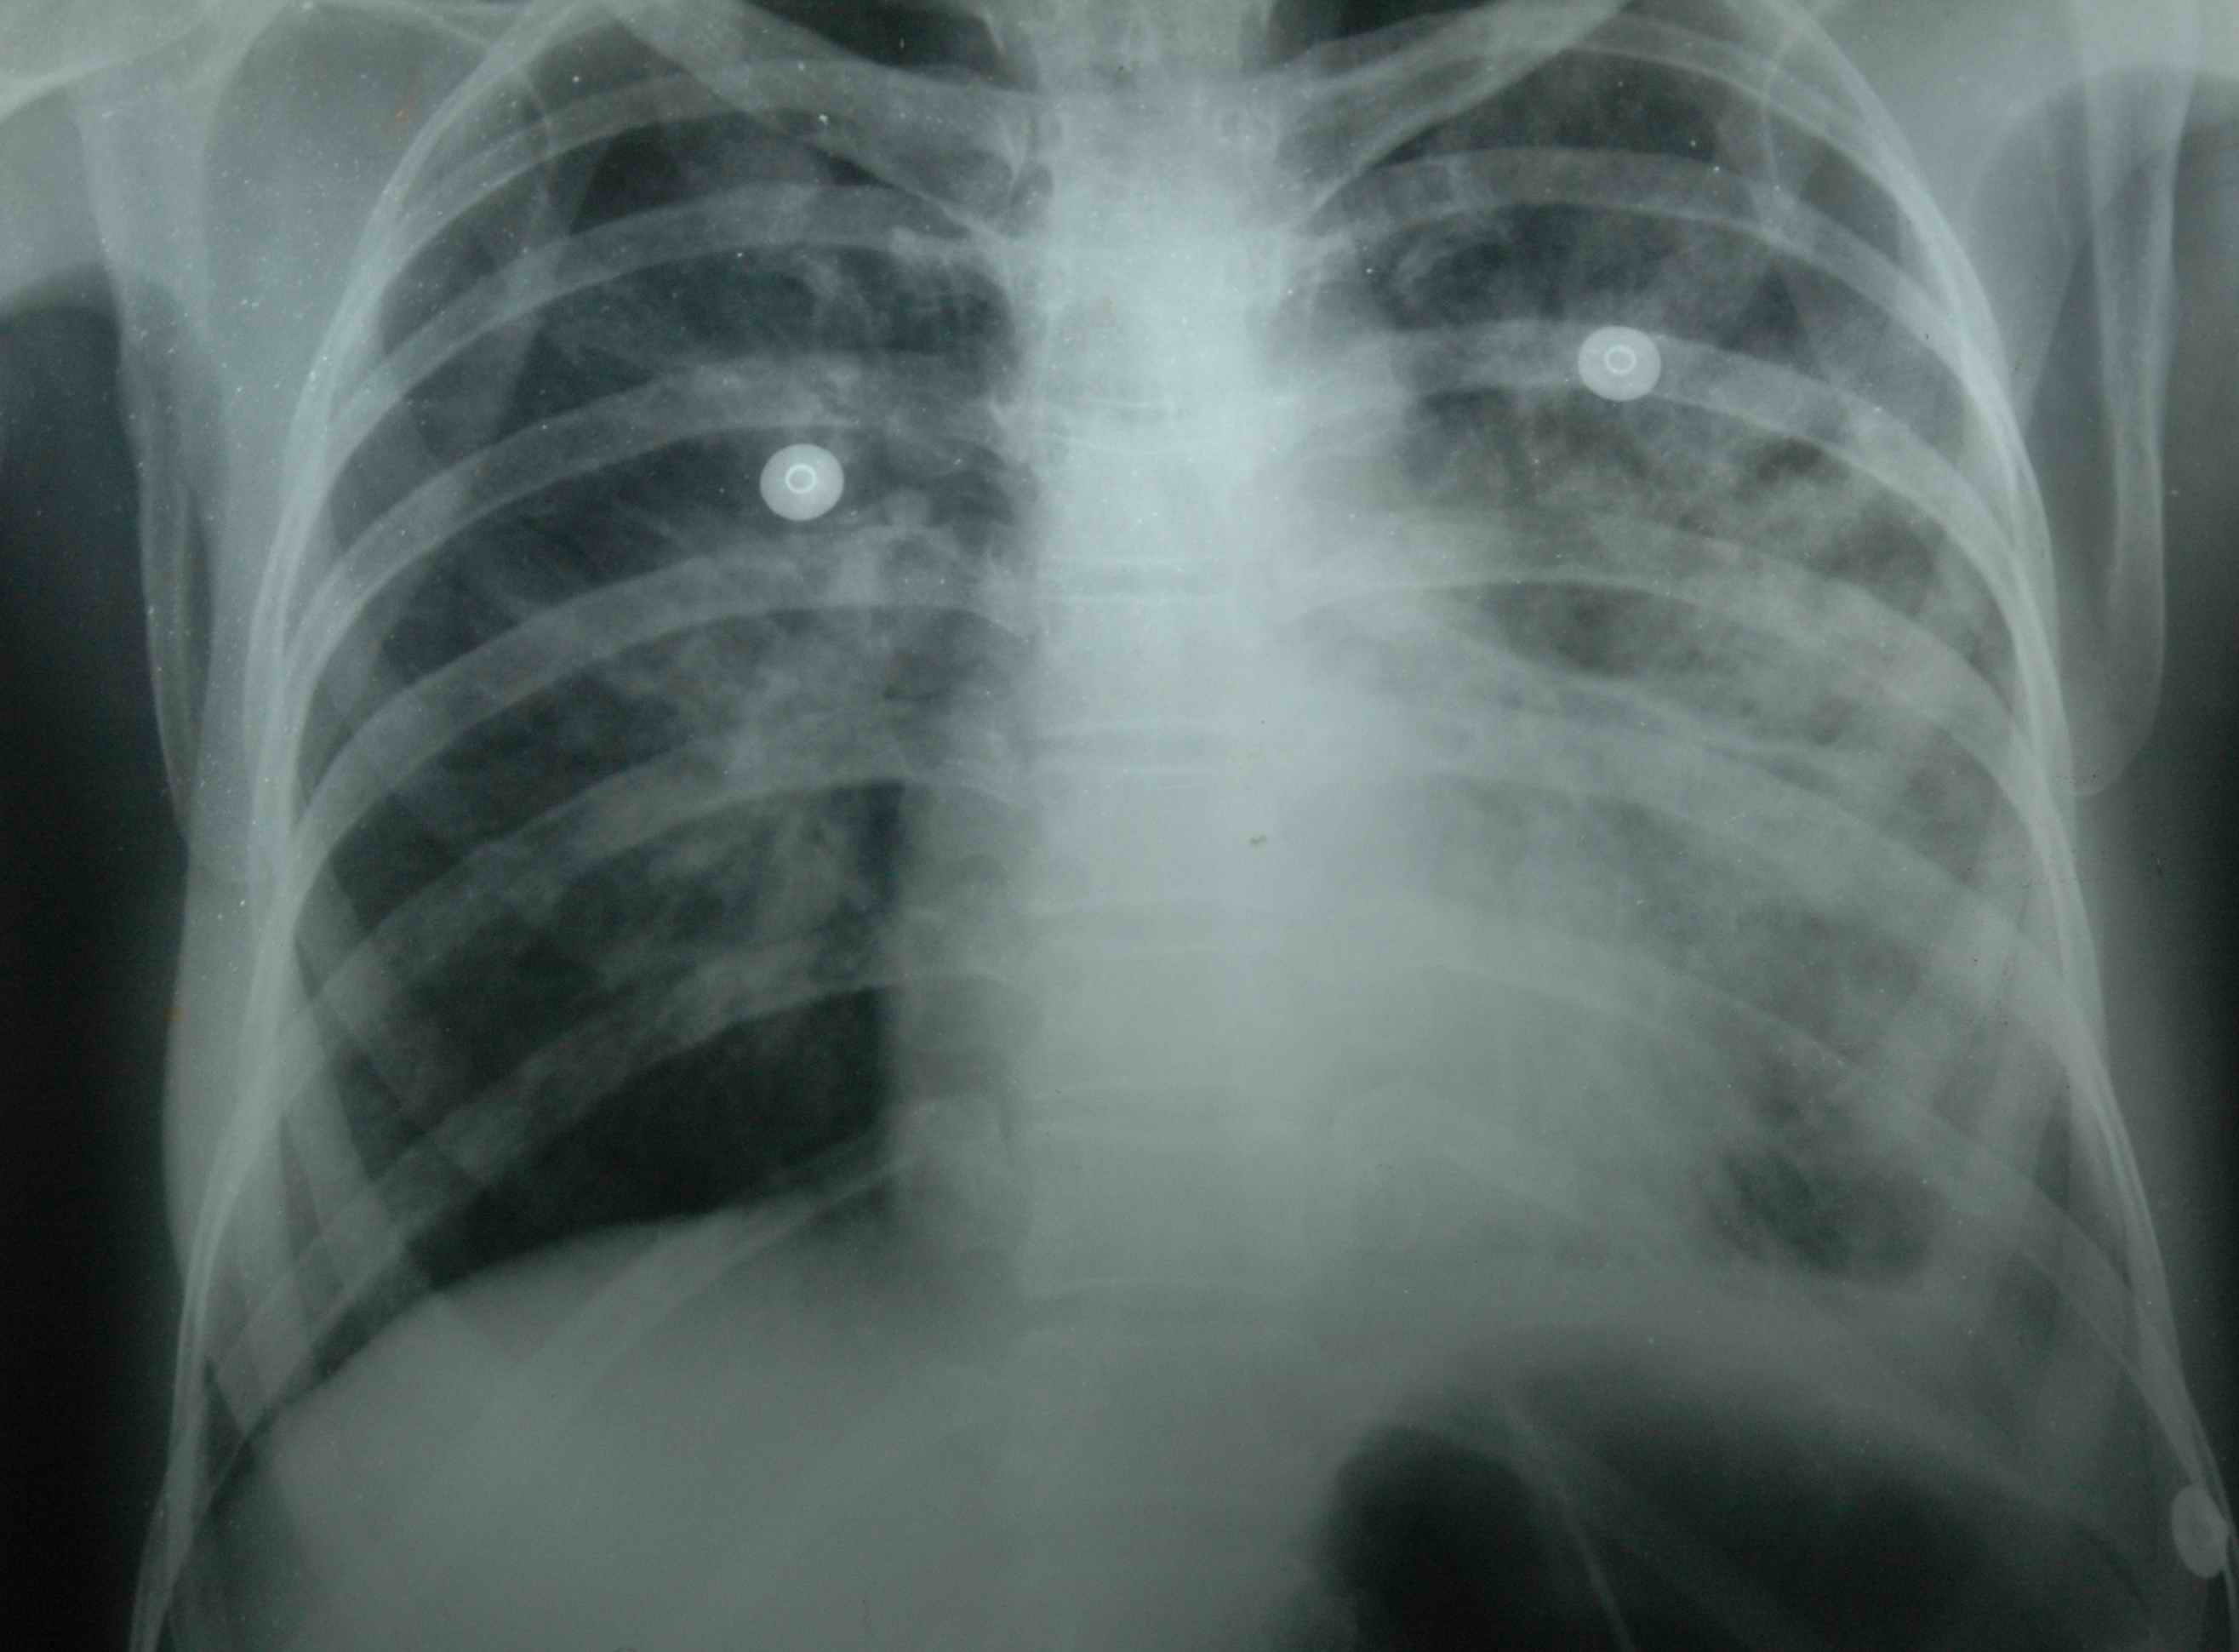

I joined PHC Poladpur at Raigad district 20 KM away from PHC Birwadi. In August 1983, a 7 year lone child of a person had scorpion sting with all signs and symptoms of red scorpion sting. Next day the child developed acute pulmonary edema. The father took it for granted that his son was going to die, because deaths due to scorpion stings were taken as a routine fact of life. As soon as the parents saw the typical symptoms of scorpion bite - priapism, cold extremities and dyspnoea - they called all close relatives and started preparations for funeral! They automatically assumed the child was going to die in next few hours. Nobody was ready to take the victim for treatment to the tertiary care hospital Mumbai. Surprisingly even when I took a few cases at a big tertiary hospital, the professors and registrars used to ask me for advice for further management. In the current case, my wife (MBBS) and I decided to use SNP. I took permission from the father. With deep sorrow he consented, and told me to try my best. I gave SNP to the child, and we both (husband and wife) sat by the side of child observing the drip. We took BP every five minutes (at that time scalp vein, intracathe, micro vein set, infusion pump etc were not available). We used to reuse the rubber intravenous set by boiling. To our great joy, the child recovered from pulmonary edema within 12 hours. I was mad with joy and almost instinctively started dancing! That was the first case which recovered from pulmonary edema under my care, with such basic amenities. Ironically, on the very same day, I received telegraph from my village regarding demise of my father.

It was a moral dilemma for me. Should I attend the funeral of my father, who had helped me become what I am today, or should I stay where I was to treat the child? After a few moments of uncertainly, the solution flashed in my mind. I would follow the Hippocratic Oath, and stay back to care for the child. Thus, strange as it may seem to all, I did not attend the funeral of my father; instead I continued to treat this child. I am sure, my father's soul, wherever it is, must have approved my action. In just one month 65 cases recovered from pulmonary edema by SNP under my care. But this was not the solution. Then again I read the medical littérateurs on refractory pulmonary edema in the KEM, JJ hospital library Mumbai, and noticed that prazosin a postsynaptic alpha -1 blocker is called oral SNP. Hence I started using prazosin and fatality was reduced to <1% ( Lancet 1986) .